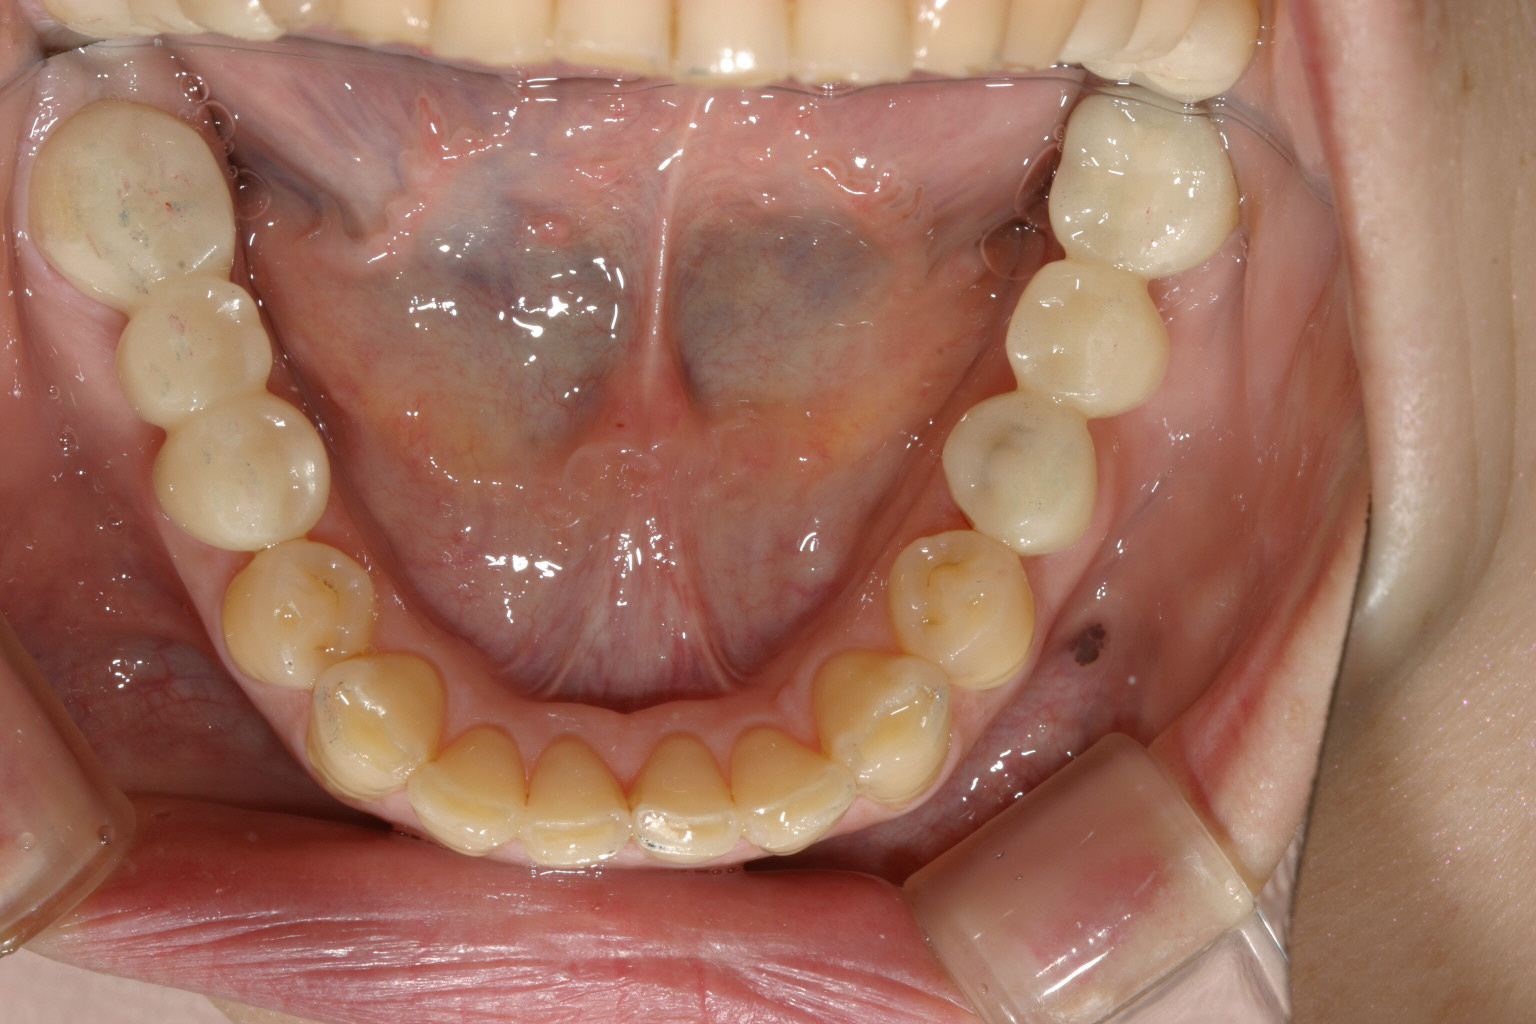

下顎も奥歯の両サイドを適切な高さを与えてブリッジにしました。

上下臼歯部のブリッジで高さを調節するとこの様に下顎が前に出て来る為この様に出っ歯観が改善します。 臼歯部のブリッジ触っただけですよ! 矯正治療は一切してないです。